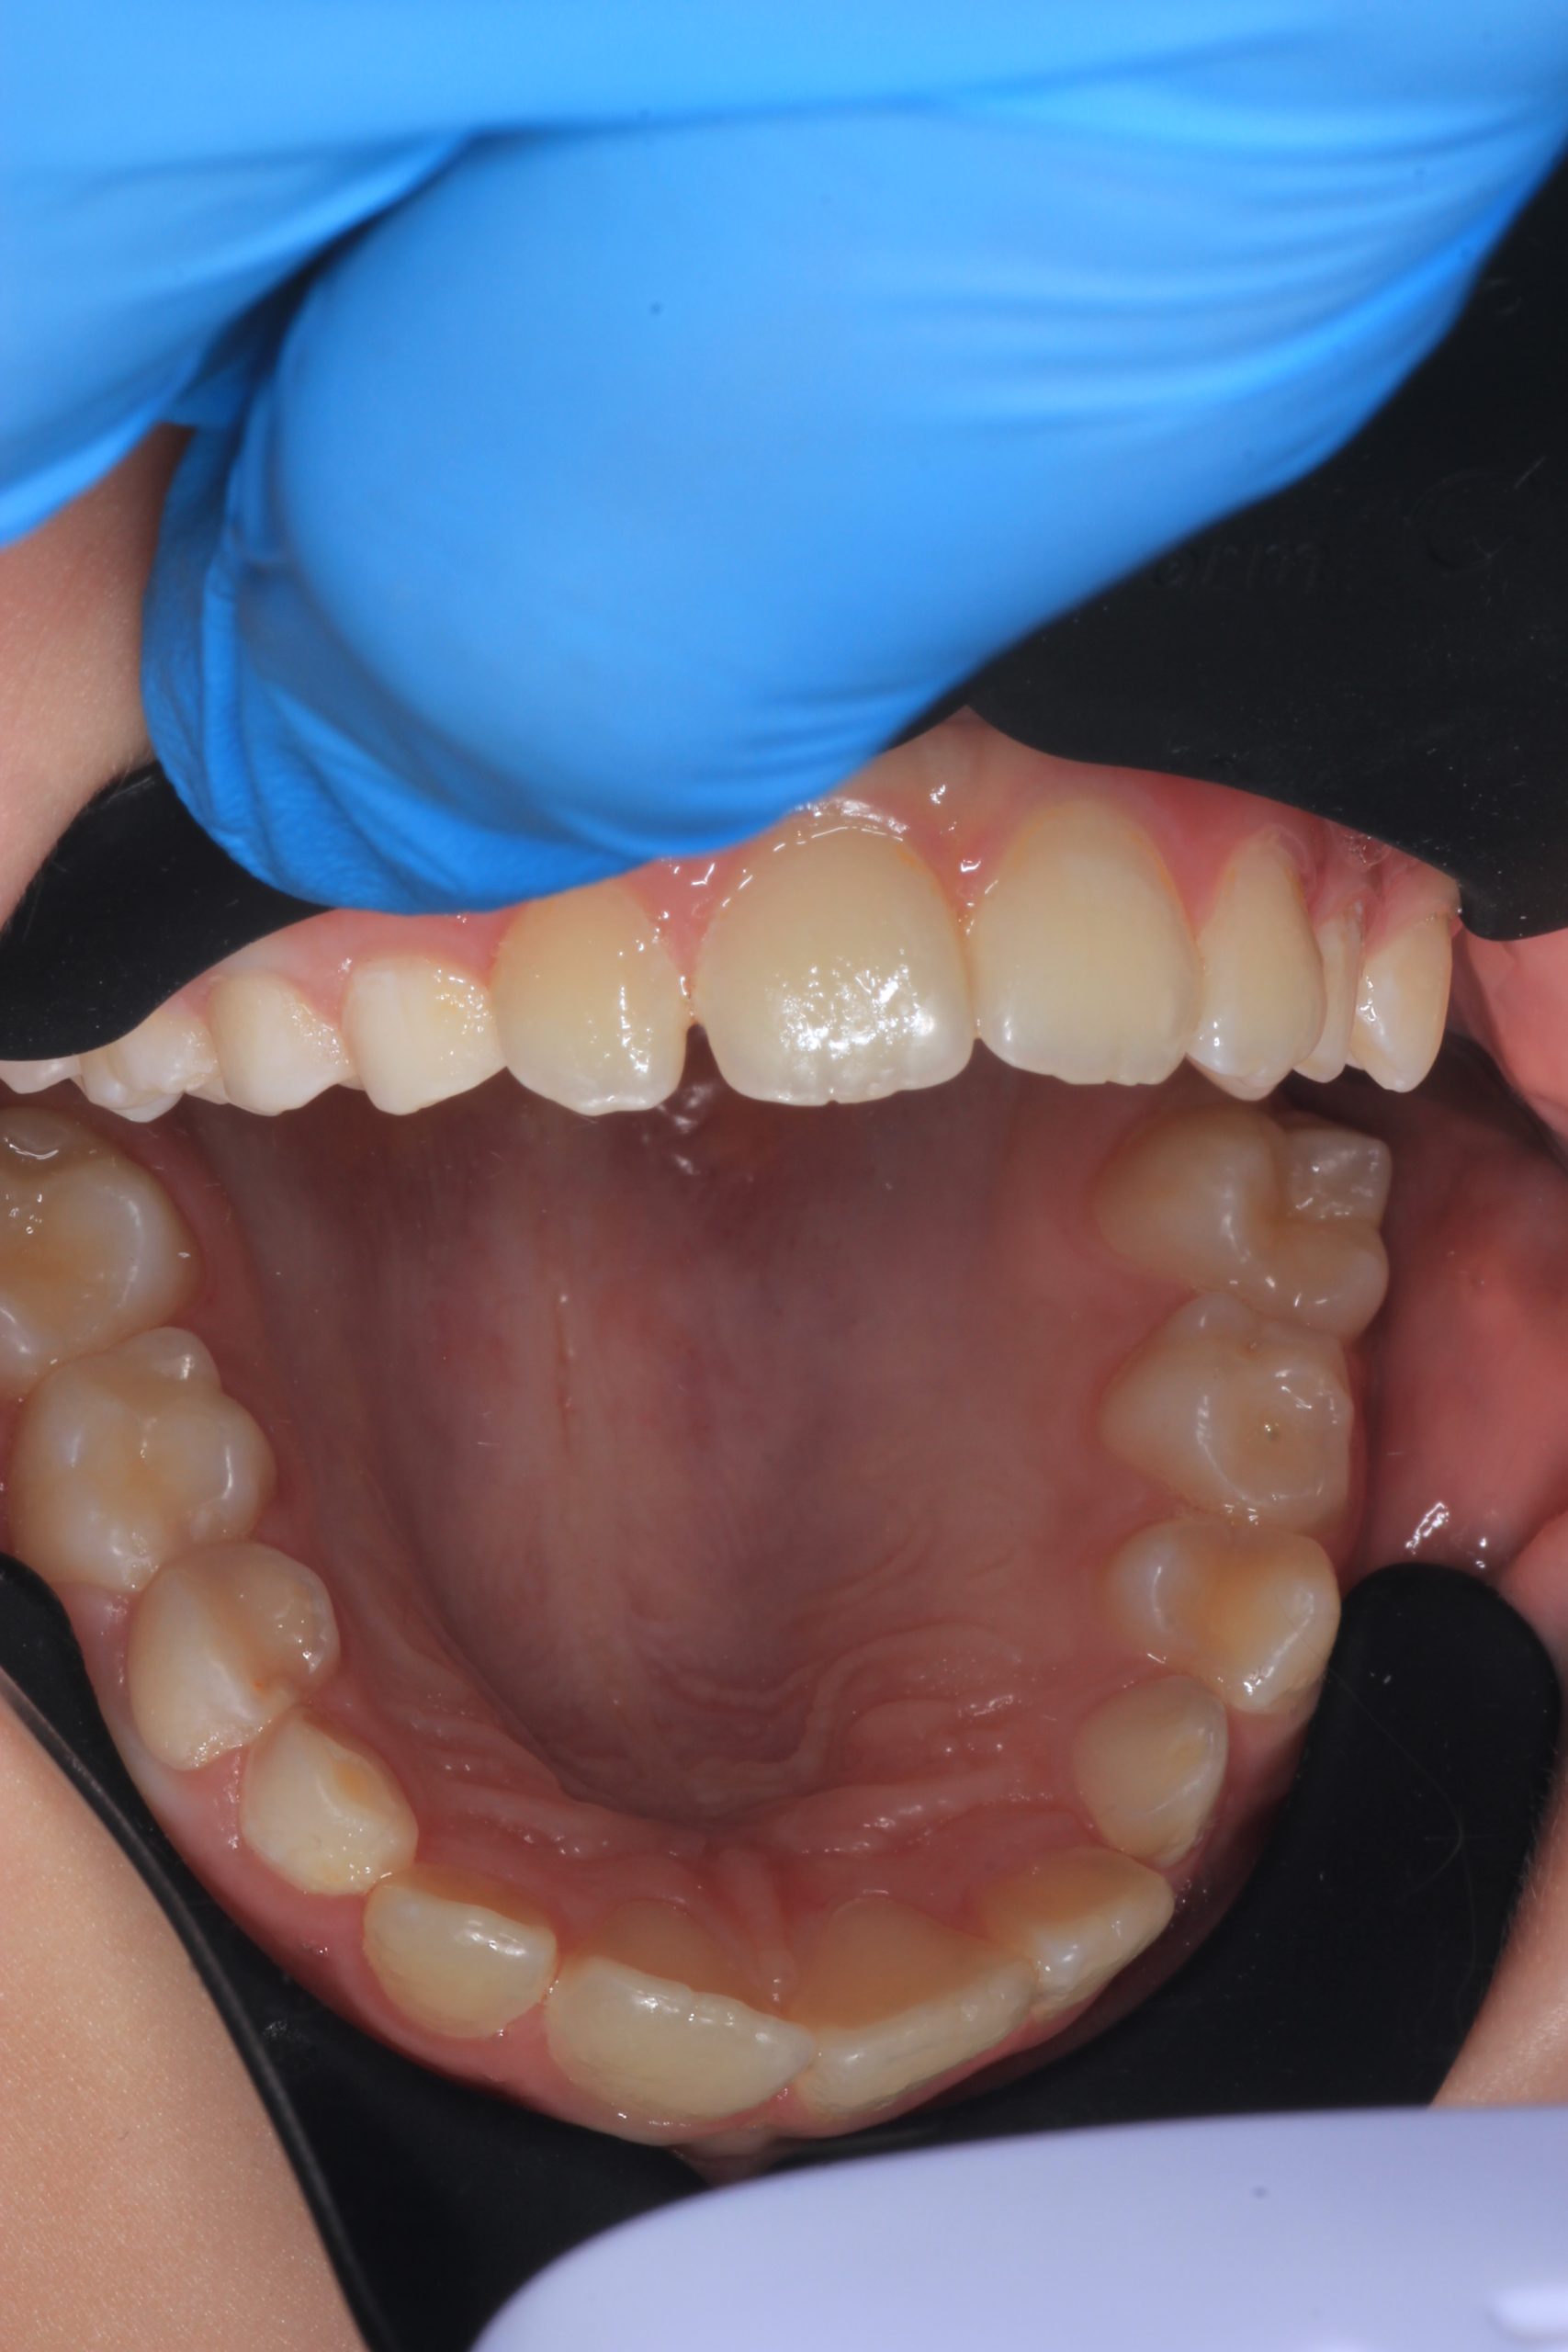

- Detailed Examination

We examine the condition of teeth, gums, and bite. - Plaque Disclosure with Special Indicators

Areas that weren’t cleaned well appear purple. The darker the shade, the older the plaque. This helps both kids and parents understand where brushing needs to improve. - Brushing Training & Home Care Tools Selection